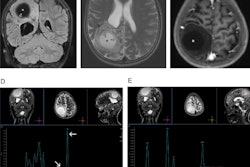

A 60-year-old man known to have HIV presented with seizures. The solid calcifications on noncontrast enhanced CT (NCECT) at the right frontal (left), left basal ganglia (middle), and right parietal areas (right) represent sequela following treatment for documented toxoplasmosis. All images courtesy of Dr. Froilan Celzo.

Same patient: Coronal (left) and sagittal (right) 3D reconstructions are shown.Also known as cerebral calculi, brain stones may be extra- or intra-axial in location. Extra-axial brain stones comprise tumors and exaggerated physiological calcifications, while intra-axial calcifications can be classified under neoplastic, vascular, infectious, congenital, and endocrine/metabolic etiologies, they wrotein an article published online on 11 September by Insights into Imaging.

The dense calcifications seen in patients with congenital toxoplasmosis can also have a random distribution, with lesion sizes that correlate with the duration of infection. Treatment can result in shrinkage and even resolution of these calcifications (see figure).